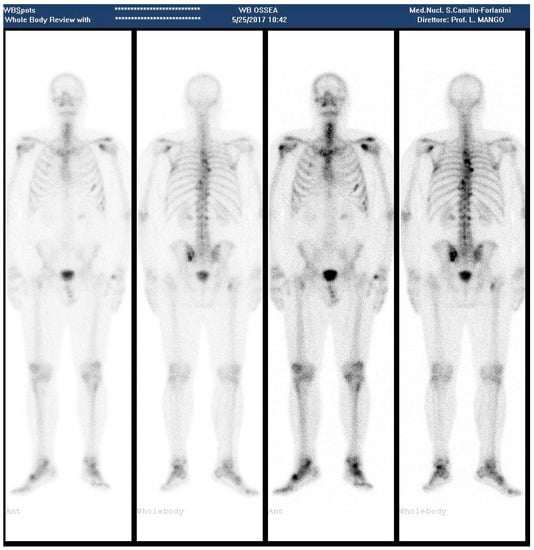

In April, PSA levels elevated to 23.95 ng/mL and in May to 47.23 ng/mL, and a bone scan revealed vertebral hyperconcentration in D3, D5; left-cost-vertebral articulation of D8 at level of the right iliac crest; slight increase of activity in the left sacro-iliac region (Figure 3).

Figure 3.

(May 2017—Bone scan 1 year after the last 223RaCl2 cycle, showing appearance of new metastatic sites).